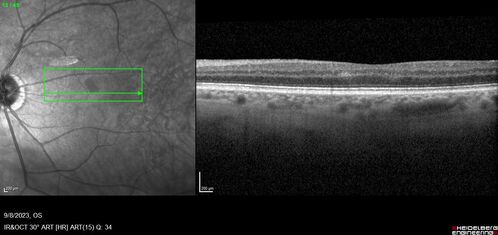

Paracentral acute middle maculopathy - isolated

83 year old man New spot in the vision yesterday left eye.

Medical Hx: Pure Hypercholesterolemia

Systemic Meds: Crestor.

VA OD: Dcc20/20

VA OS: Dcc20/20

IOP: TP: OD:19 OS:10

Isolated PAMM lesion